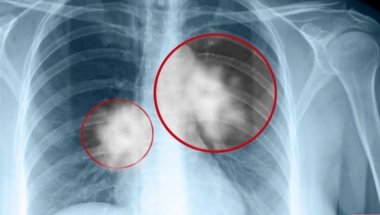

Rak pluća predstavlja vodeći uzrok smrtnosti od svih maligniteta, te brojke pokazuju da godišnje od raka pluća oboli oko 7.000 ljudi, a umre oko 5.000.

-Važno je bolest otkriti u ranoj fazi kako bi se omogućilo lakše lečenje. Nažalost, mnogi se jave kasno, kada boelst već odmakne i kada automatski postajemo ograničeni što se tiče lečenja. Nekih 70 odsto pacijenata dođe kada je bolest već odmajla, dodaje dr Stjepanović.

Od simptoma javlja se kašalj, sa ili bez iskašljavanja, malaskalost, gubitak na težini, dok se u nekim odmaklim stadijumima bolesti javlja i iskašljavanje krvi.

-Kako su pluća veliki organ, tako i bolest u početku ne daje neke specifične simptome, zbog toga i kažemo da svaki kašalj treba ispitati kako bismo utvrdili o čemu se tačno radi kako bismo pristupili lečenju na pravi način. Dijagnoza je isključivo patohistološka, tako određujemo koji tip raka pluća u pitanju. To je važno jer danas postoje savremeni lekovi, imuno i biološka terapija, gde se bolest uspešnije drži pod kontrolom, objašnjava dr Stjepanović.